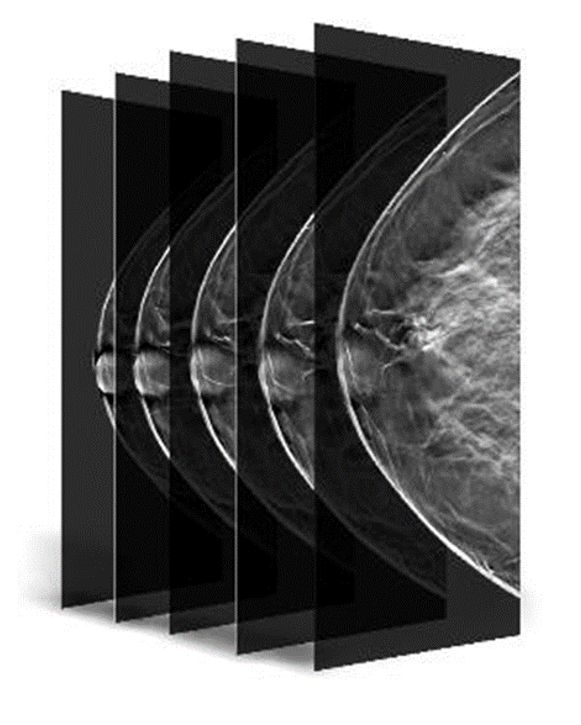

Gelişmiş 3D Tomosentez Teknolojisi

Hologic Selenia® Dimensions, FDA onaylı Genius™ 3D tomosentez teknolojisi ile meme dokusunu yüksek çözünürlükte katman katman tarar. Bu ileri teknoloji, geleneksel 2D mamografiye kıyasla meme kanserini %20 ile %65 arasında daha yüksek oranda tespit ederek erken teşhiste önemli bir avantaj sunar. Klinik çalışmalar, bu sistemin yalancı pozitif çağrı oranlarını %40’a kadar azaltarak gereksiz biyopsi sayısının düşürülmesini sağladığını ortaya koymaktadır. Özellikle yoğun ve karmaşık meme yapısına sahip hastalarda, lezyonların daha net görünmesini mümkün kılarak radyologların tanı güvenilirliğini artırır.